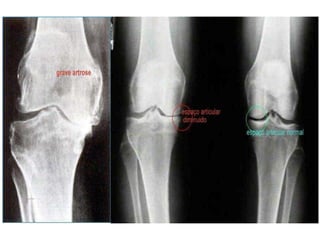

Raio X : utilizado para classificar a doença.

Graduar a severidade do dano estrutural.

Lesões vão desde: ausência de alterações,

visíveis à radiografia e até

estágios avançados como:

•

A presença de cistos ósseos.

Osteófitos exuberantes.

Redução do espaço articular.

Esclerose do osso subcondral.